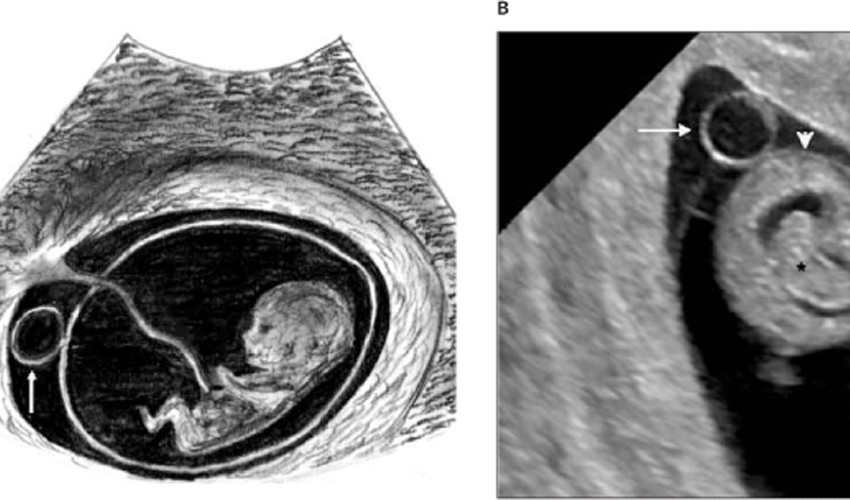

Yolk kesesi ultrason görüntüsü

Aşağıdaki görselle okla gösterilen alanlarda yolk kesesini görebilirsin.